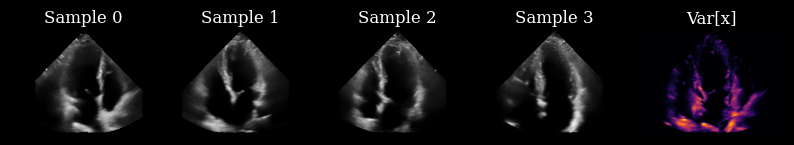

Visualize target sequence

Here we load a sequence of ultrasound frames from the CAMUS validation set. This will be our ‘ground truth’ target sequence, that the agent will need to reconstruct from a small budget of focused scan lines

[7]:

scan_convert = Pipeline([ScanConvert(order=2, jit_compile=False)])

parameters = {

"theta_range": [-0.78, 0.78],  # [-45, 45] in radians

"rho_range": [0, 1],

}

parameters = scan_convert.prepare_parameters(**parameters)

data_sc = scan_convert(data=data, **parameters)["data"]

n_frames_to_plot = 5

fig, _ = plot_image_grid(

data_sc[:n_frames_to_plot],

titles=[f"t={t}" for t in range(n_frames_to_plot)],

ncols=n_frames_to_plot,

remove_axis=True,

vmin=-1,

vmax=1,

)

zea: WARNING GPU support for order > 1 is not available. Disabling jit for ScanConvert.

../../_images/notebooks_agent_agent_example_12_1.png